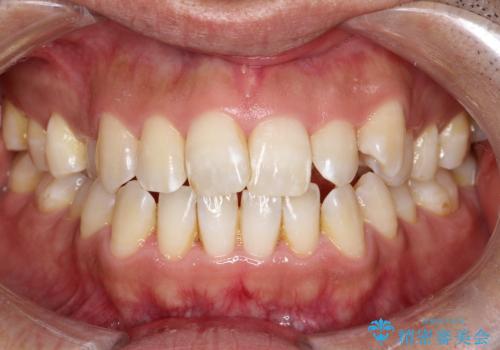

翼状捻転と叢生を矯正で改善

- 治療計画

治療では、審美ワイヤーを使用し、目立ちにくく配慮しながら矯正を進めました。上顎にリンガルアーチと矯正用アンカースクリューを用いて臼歯部を安定的に遠心移動させ、歯列全体のスペースを確保しました。その後、回転していた前歯を正しい位置に配列し、全体的な歯並びの改善を行いました。治療中は、装置の適切な管理と口腔衛生を徹底することが重要でした。結果として、見た目だけでなく機能的にも優れた歯列を実現することができ、患者様にもご満足いただけました。